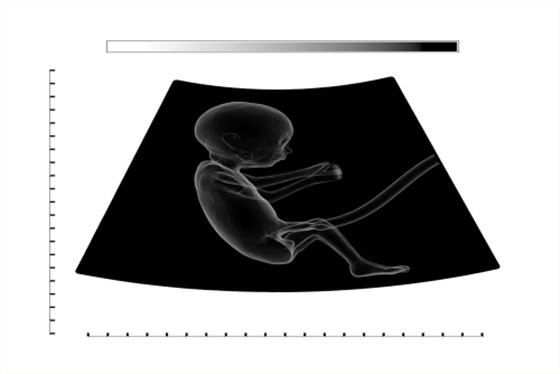

產前超聲檢查1級,通常指的是孕婦進行超聲檢查時,發現胎兒身體發育基本正常,并沒有發現胎兒畸形的現象。臨床上根據胎兒畸形的程度,將產前超聲檢查分為4級,而不是1級。

1、1級:又稱為擦頸部皮膚超聲檢查,通過B超檢查可以觀察到胎兒頸部皮膚有少量的改變,如頸部可見線樣的淋巴結節,但是結構較清晰,并沒有發現胎兒結構異常的情況,通常屬于正常的胎兒狀態;

2、2級:屬于超聲檢查中的第二級,指的是胎兒出現輕微的畸形,但外觀并不明顯,如身體的四肢、面部、頭部等部位,存在較小的畸形;

3、3級:又稱為可疑性畸形,在進行超聲檢查時,可以看到胎兒有明顯的結構異常以及嚴重的畸形,如重度的腦積水、胸腔積液、腹腔積液以及心腔畸形等;

4、4級:通常指的是比較嚴重的畸形,孕婦在進行超聲檢查時,可以看到胎兒存在身體明顯畸形,如嚴重的唇腭裂、重度腦積水以及心臟畸形等。

孕婦在進行產前超聲檢查時不需要空腹,建議穿著寬松的衣物,可以在超聲檢查時戴上手套,此時超聲檢查結果更為準確。在進行產前超聲檢查時,如果發現異常情況,應及時進行處理,以免增加不良妊娠結局。